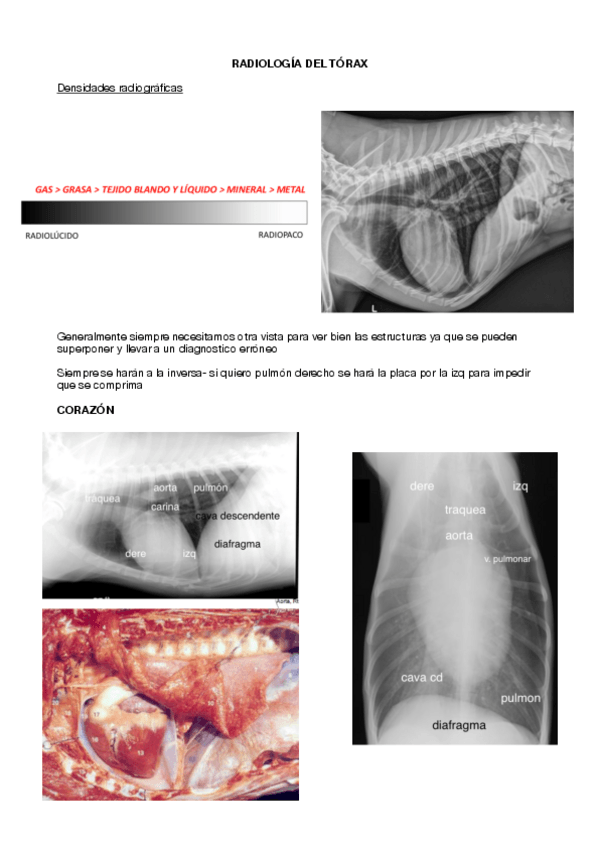

radiologías

7 páginas